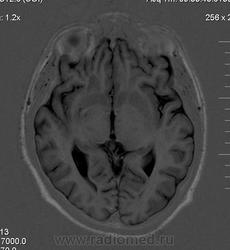

Мужчина 32 лет. Из анамнеза: перинатальное повреждение ЦНС, ДЦП, дизартрия, правосторонний верхний монопарез. С 16 лет приступы эпилепсии.

Аплазия прозрачной перегородки. Шизэнцефалия с открытыми краями в лобно-теменной области слева. Шизэнцефалия с закрытыми краями в лобной области справа? Утолщение коры по контуру расщелин и в области глазничной извилины правой лобной доли. Микрогирия? Гиперостоз костей свода черепа. Уважаемые коллеги, возможно я ошибаюсь, или есть еще аномалия?

сочетания отсутствия прозрачной перегородки и дисплазии ( разно степени выраженности) зрительных неровов  указывает на септоптическую дисплазию-нарушение развития в области средней линии , сопровождается мнггими другими структурными аномалиями, чаще шизэнцефалией.

На мой взгляд, полимикрогирия двусторонняя (конвекситальные отделы дорзальных отделов лобных долей и частично теменных, а также в базальном отделе полюса правой лобной доли) + закрытая шизенцефалия левой лобно-теменной области. Аплазия прозрачной перегородки (как признаки лобарной голопрозенцефалии).